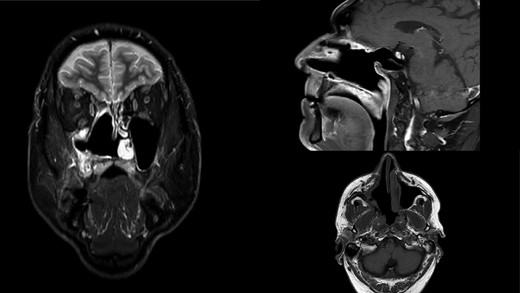

A 66-year-old patient with a history of heart disease presented to our hospital with recurrent epistaxis, hyposmia and nasal congestion. On examination, the patient was found with an ulcer-proliferative mass that obstructed the entire right nasal cavity spreading from the epipharynx to the oropharynx. No lymphadenopathy was detectable. Computerized tomography (CT) scan of the head and neck region showed expansive mass primarily in the right maxillary sinus spreading throughout the ostiomeatal complex, infiltrating the septum, all ethmoid cells, entering into the frontal sinus through frontoethmoidal recess and penetrating the nasopharynx. The soft palate was suppressed by the described mass and the initial infiltration of the right pterygoid muscles was also visible (Fig. 1). A biopsy revealed tumor cells built up of a dense mass of small blue cells with round and hyperchromatic nuclei with mitosis. Tumor cells had an ill-defined border and grew into syncytia. Desmoplasia was abundant, with areas of osteoid or chondro-osteoid-like material deposition. Immunohistochemically tumor cells were positive for vimentin, CD99, ERG, FLI-1, MDM2, CDK4, CD56, CK 5/6 and histochemically showed PAS-positive glycogen in the cytoplasm. A working diagnosis leaded to highly malignant and poorly differentiated sarcoma with elements of Ewing’s sarcoma and elements of bone differentiated tumor. Before proceeding with wide surgical resection, the patient received seven cycles of neoadjuvant chemotherapy with paclitaxel and carboplatin. The aggressive tumor growth was stopped, but tumor mass was minimally reduced. Surgical resection of the tumor was performed by mid-face degloving approach with temporary ostectomy of the frontal process of the maxilla and the anterior wall of the maxillary sinus. Medial maxillectomy and resection of the tumor were then performed. The tumor extended from the lateral wall of the maxillary sinus to the anterior part of the inferior nasal turbinate up to 5 cm below the epipharynx into the oropharynx. The posterior part of the septum on the rostrum was removed and bilateral ethmoidectomy was performed. The lamina papyracea was also resected; the skull base was inspected and was completely free of tumor. The part of the nasolacrimal canal that was in contact with the tumor was resected and a small stump was left on the lacrimal sac on which marsupialization was performed. Surrounding margins were free of tumor cells on the intraoperative frozen section (Fig. 2).

Initial CT scan of the head and neck region in coronal, axial and sagittal view show expansive formation predominantly in the right half of the paranasal sinuses. Right maxillary sinus is completely filled with tumor mass as well as right nasal cavity with infiltration of the septum, all ethmoid cells and the frontal sinus through frontoethmoid recess. Sagittal view show tumor spread in the nasopharynx.